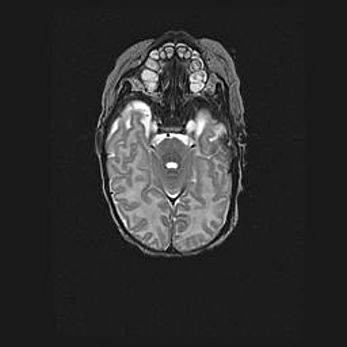

Аномалия Денди-Уокера. Признаки гипоплазии мозолистого тела.

Возраст: 5 месяцев 3 дня

Вес: 5550 г

Пол: мужской

Окружность головы: 39 см

Срок гестации: 40 недель

Аномалия Денди-Уокера – это порок развития головного мозга, для которого характерна триада симптомов: гипотрофия или аплазия червя мозжечка и/или полушарий мозжечка, расширение четвёртого желудочка с формированием ликворной кисты задней черепной ямки, гипертензионная гидроцефалия различной степени.

Гипоплазия мозолистого тела относится к дефектам внутриутробного этапа развития мозговой ткани, возникающим в процессе закладки структур головного мозга, что происходит на начальных этапах развития эмбриона.